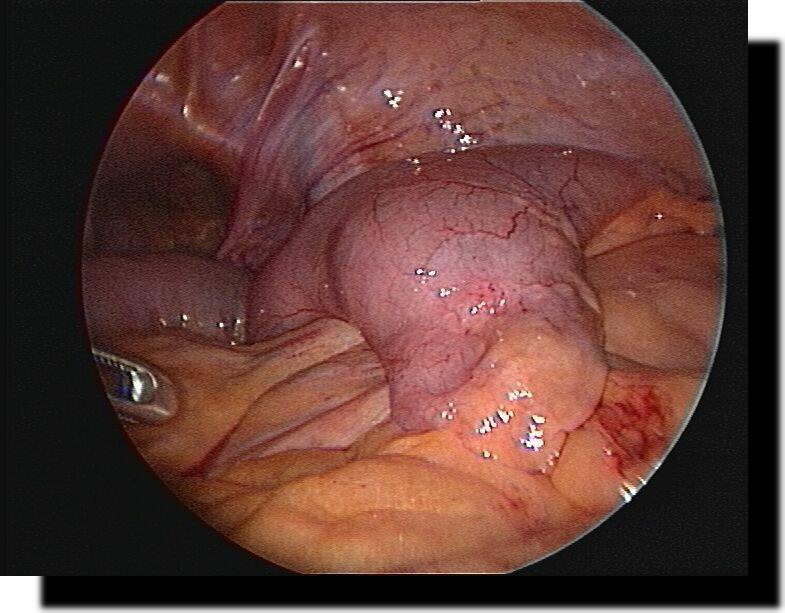

Leberhämangiom